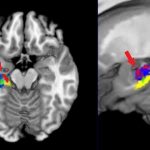

Study: Three ways studying organic chemistry changes the brain — (Details)

Academic learning is about gaining new knowledge and skill, but only recently has it been possible to see new knowledge appear in a...